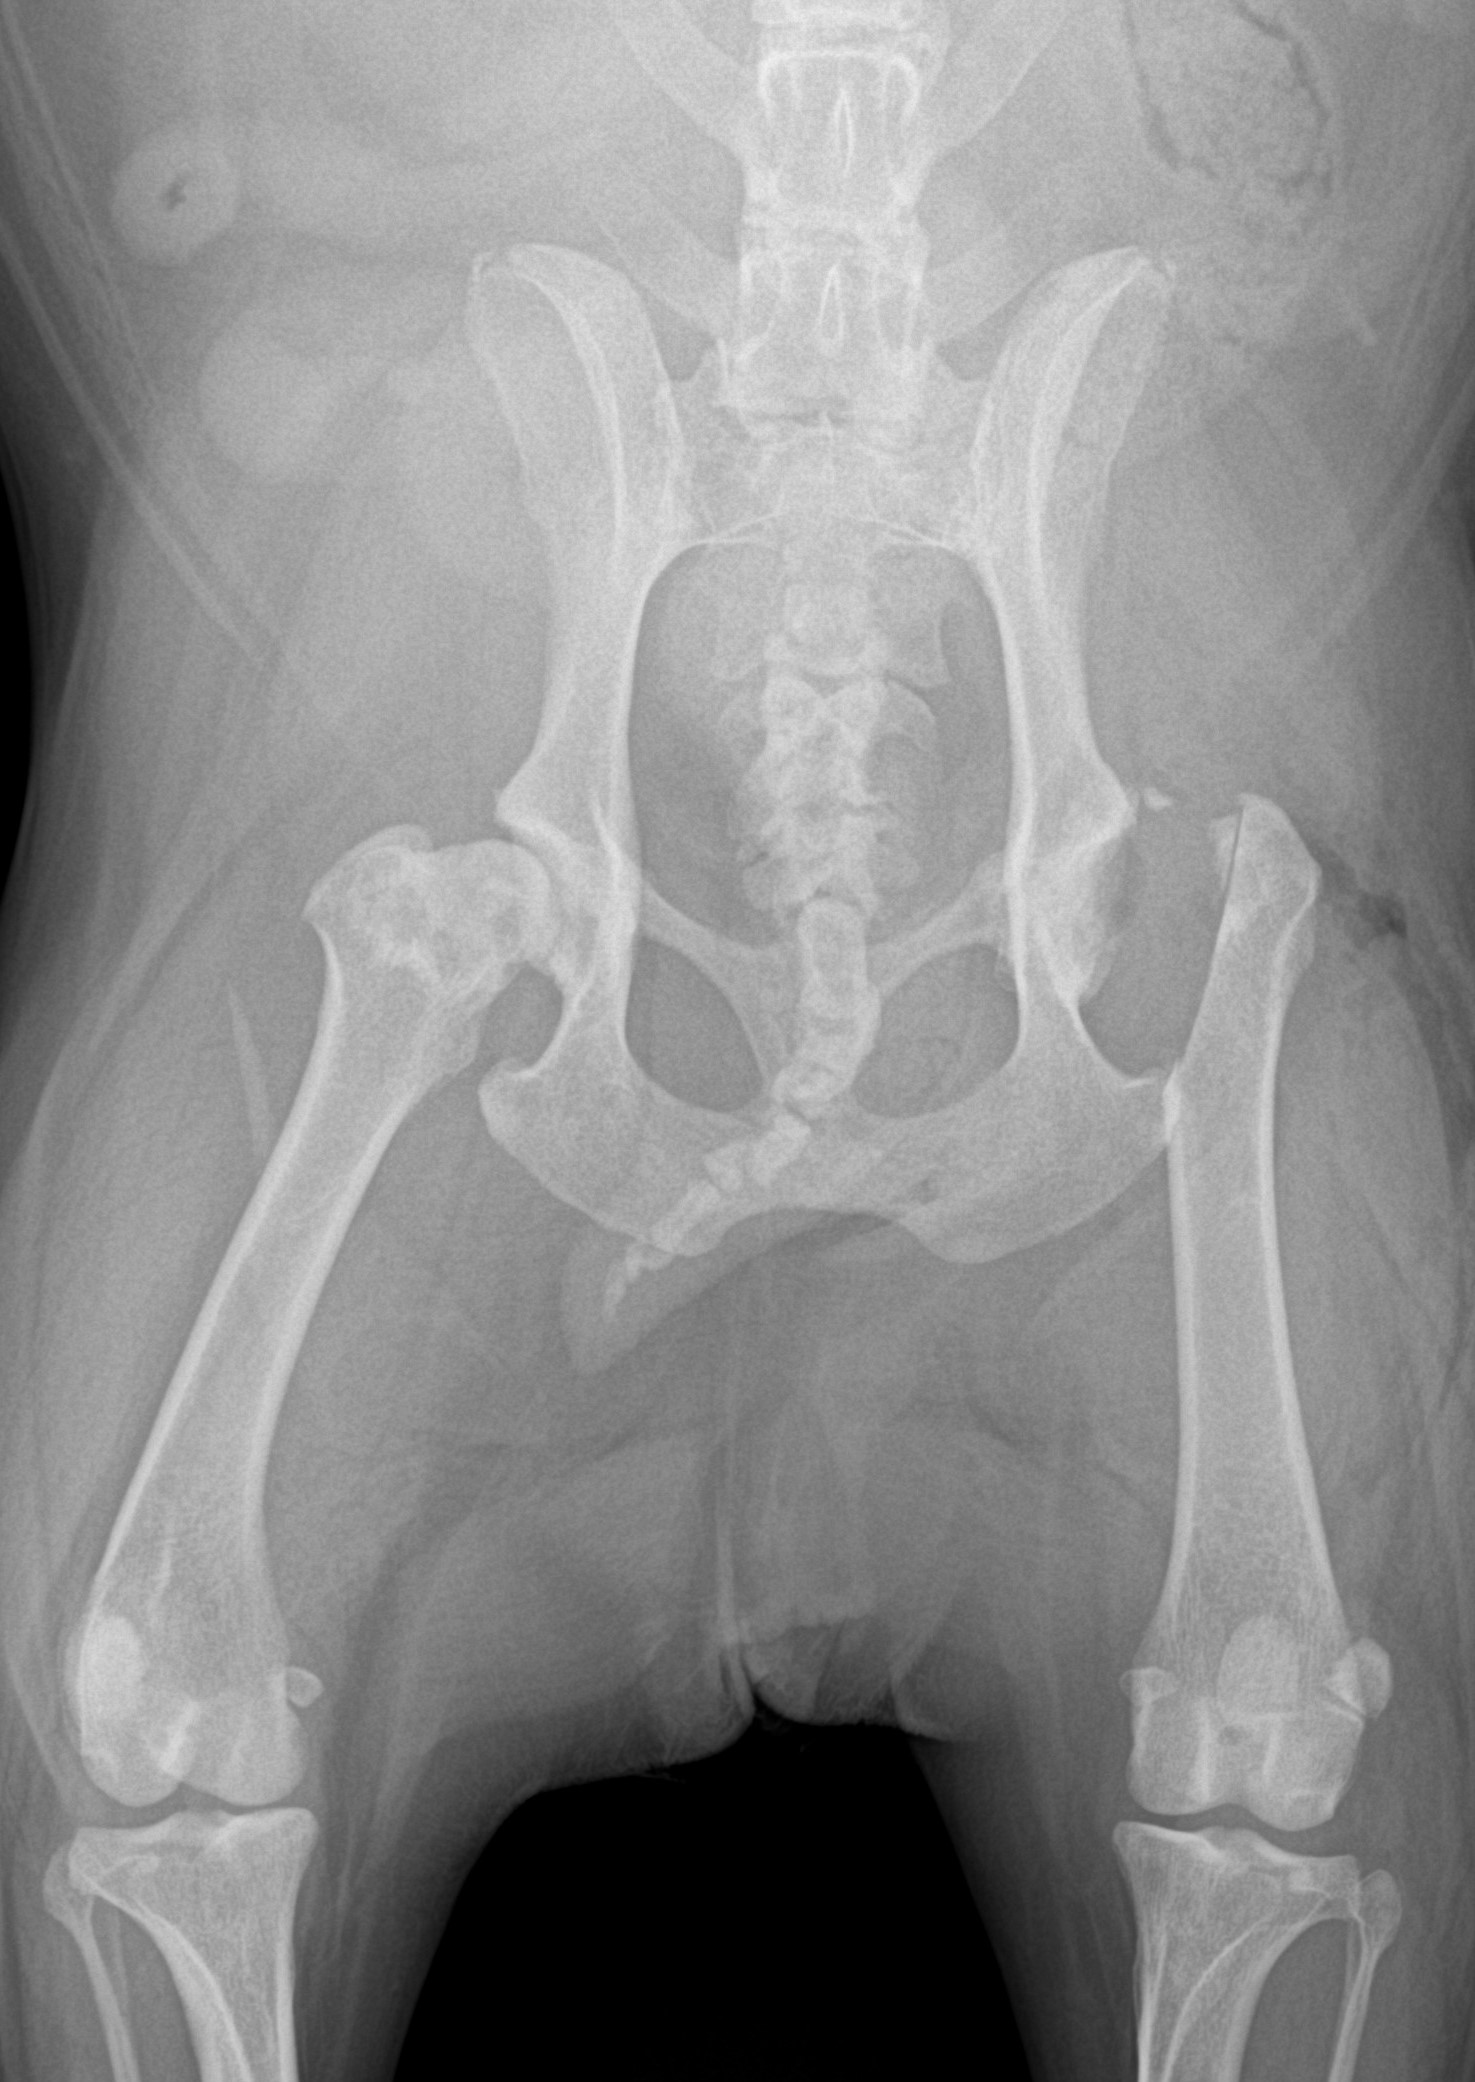

Resekce hlavice stehenní kosti při silné artróze